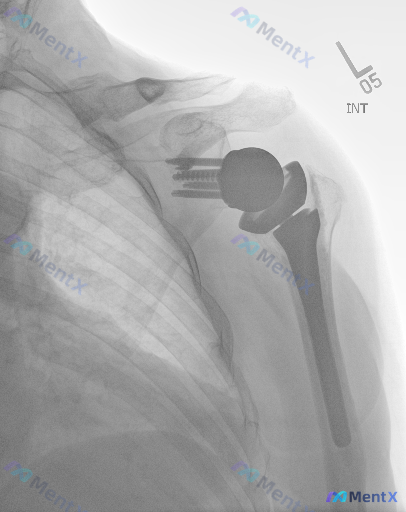

整理到一张左侧肩部正位X光片及配套的完整分析报告,大家可以先看核心影像信息: - 影像显示左侧肩关节已行肱骨头置换术(半肩置换),可见金属假体占据肱骨近端位置 - 肱骨假体柄位于肱骨髓腔内,假体头与关节盂相对,未见明显假体松动、透亮带或假体周围骨折 - 显影范围内的锁骨、肩峰、喙突及部分肋骨未见明显...

整理到一张左肩正位X光片的阅片资料,大家可以先看一下核心表现: - 左侧肩关节已行置换术,肱骨头为金属假体,有髓内柄 - 假体位置看起来居中,肩胛盂对位尚可 - 假体周围未见明显透亮线 - 关节盂附近和下胸壁还有点小的金属高密度影 - 没看到明确的急性骨折、脱位或恶性骨破坏 不过资料里提到了一个点:...

整理了一份左肩关节反式置换术后的X光正位片资料,影像科的直接结论是“假体位置良好,未见明确的形态学异常(如假体移位、急性骨折、明显的骨溶解或软组织肿胀)”。 但这份分析报告后面的部分很有意思——它特别强调了“影像学的静态完美”与“临床功能的动态不确定性”之间的分离,还把“亚临床假体周围感染”列为了最...

整理到一份影像资料:左侧肩关节置换术后的腋位(Cross-table)X光片。 先看这份影像的客观描述: - 人工肱骨头假体及柄部位置良好,未见明显松动、断裂或透亮带 - 盂肱关节对位正常,无脱位/半脱位 - 假体周围骨质密度均匀,未见溶骨性破坏或明显骨赘 - 周围软组织轮廓基本正常,无明显钙化 影...